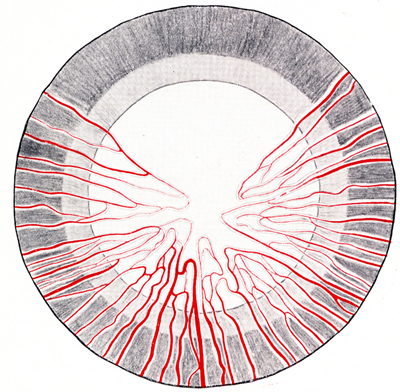

Aspecto de la membrana pupilar en un feto humano de 5 meses de gestación.

Foto tomada de: Ida Mann ; The development of the Human Eye. 1969. Grune & Straton Inc N.Y

Diagrama de la apariencia del Iris y la Membrana Pupilar, de un feto humano de 7 meses,vista desde el frente.

Foto tomada de: Ida Mann ; The development of the Human Eye. 1969. Grune & Straton Inc N.Y